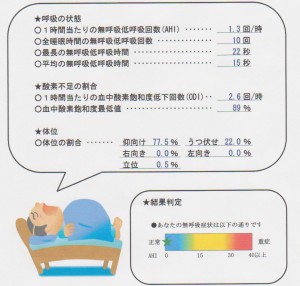

とある大学病院の呼吸器内科から紹介されたKさん。中等度の睡眠時無呼吸との診断であった。睡眠時の1時間当たりの無呼吸低呼吸回数は26回(大学病院での検査値)であった。マウスピースにより当院にある簡易型検査でこの値は1.3回(正常値は5以下)に落ち着いた。Kさんも、周りからいびきを指摘されなくなり、日中の眠気も少なくなったとのことで、喜ばれた。マウスピースは単純な装置だが、患者さんのQOLを向上させるケースは多い。下記の資料を添付して、紹介元の病院に送った。客観的なデータを自院で出せるようになったことは、大きい。術者や患者さんの治療に対するモチベーションが上がる。(長谷川)

患者さんにお渡しする検査結果(左)マウスピース非装着時、(右)装着時